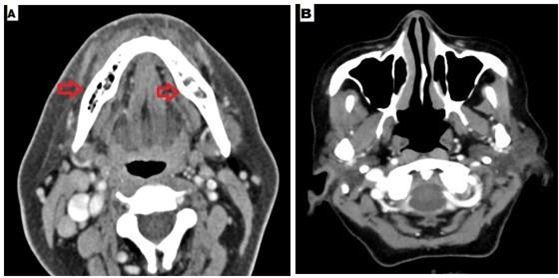

Case 4: A 49 year old lady with no prior co morbidity developed mild Covid-19 pneumonia 3 months ago and was treated with supplemental oxygen and steroids in the form of dexamethasone 6mg once a day for total 12 days. She did not require antivirals. She presented with bilateral jaw pain and numbness over the overlying skin for 3 weeks. She had no prior dental manipulation. There was no sinus symptom associated with jaw pain.

Sinus endoscopy did not reveal any mucosal disease, CT image of the sinus was also normal. HbA1C was 9.7%. Z-orthopantomogram showed bilateral mandibular erosions (Figure 5). CT showed bilateral mandibular osteomyelitis (Figure 6). Debridement was performed and histopathology revealed broad aseptate and pauciseptate fungal hyphae with obtuse angle branching. There was significant bony and angioinvasion; a characteristic feature of invasive mucormycosis. Fungal culture was negative. She was started on injection lipid emulsion amphotericin b and was continued for 2 weeks. She responded well and was switched to tablet posaconazole after 2 weeks. Serum trough level was performed after 7 days and was found to be 1483 ng/ml.

Figure 6 A- CT mandible revealed bilateral mandibular osteomyelitis with cortical expansion, B- CT paranasal sinuses – normal.